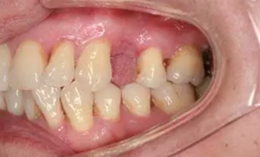

從圖1可以看出患者缺牙區(qū)的間隙充足,牙齦健康,頰側(cè)軟組織略有凹陷。

圖1 缺牙區(qū)的頰側(cè)和口內(nèi)照片